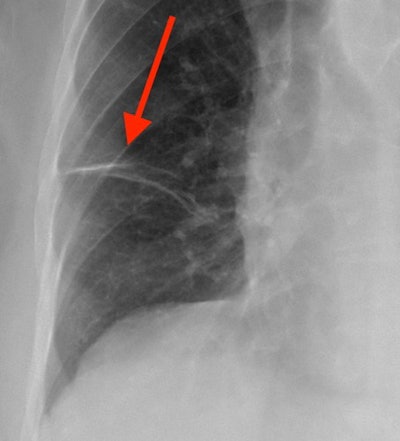

- Fibrosis/scar: Just like your skin, the lungs form scar tissue when injured or otherwise damaged. Fibrosis is synonymous with scarring, and focal scars are a common finding on chest x-rays. Small areas of scarring are often not significant, but large or diffuse scarring can impair lung function. Certain disease processes that cause diffuse fibrosis can result in significant destruction of normal lung tissue, even making a lung transplant necessary. Small focal scars often appear as linear densities on chest x-ray, while diffuse fibrosis results in an interstitial lung pattern.

- Interstitial lung pattern: An interstitial lung pattern refers to subtle thin lines and small dots interspersed throughout the lungs. Sometimes radiologists will use the term "reticular" to mean lines and "reticulonodular" to mean lines and dots together. To understand this appearance, it's time for another lung anatomy lesson. The interstitial tissues are located between the airways and alveoli previously described, and they consist of tissues that help support the lung, including blood vessels. On a normal chest x-ray, the interstitial tissues are too small to see. Only when they are abnormally thickened do they manifest as thin visible lines. Dozens of conditions can result in this appearance, with some common causes including pulmonary edema, pulmonary fibrosis, certain types of pneumonia, and autoimmune and allergic conditions.